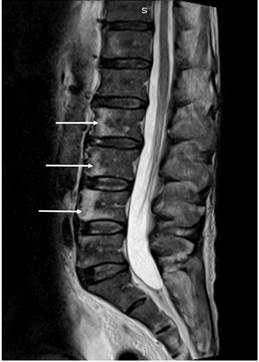

En la resonancia contrastada de la columna vertebral total se hallaron lesiones líticas en los cuerpos vertebrales L2, L3 y L4, y hueso ilíaco derecho con signos de reconversión medular (Figura 4). Durante la vigilancia clínica con cubrimiento antibiótico, se evidenció el deterioro clínico progresivo. Se realizó una colonoscopia en la que se evidenció una úlcera en la válvula ileocecal y el ciego, a la cual se le tomó una biopsia para realizar tinciones para hongos y reacción en cadena de la polimerasa (PCR) para tuberculosis. Ante el deterioro clínico con los hallazgos de múltiples órganos, se indicó el manejo con anfotericina B ante la sospecha de histoplasmosis, pero con niveles de galactomanano negativo, por lo cual se suspende al día 4 de manejo.